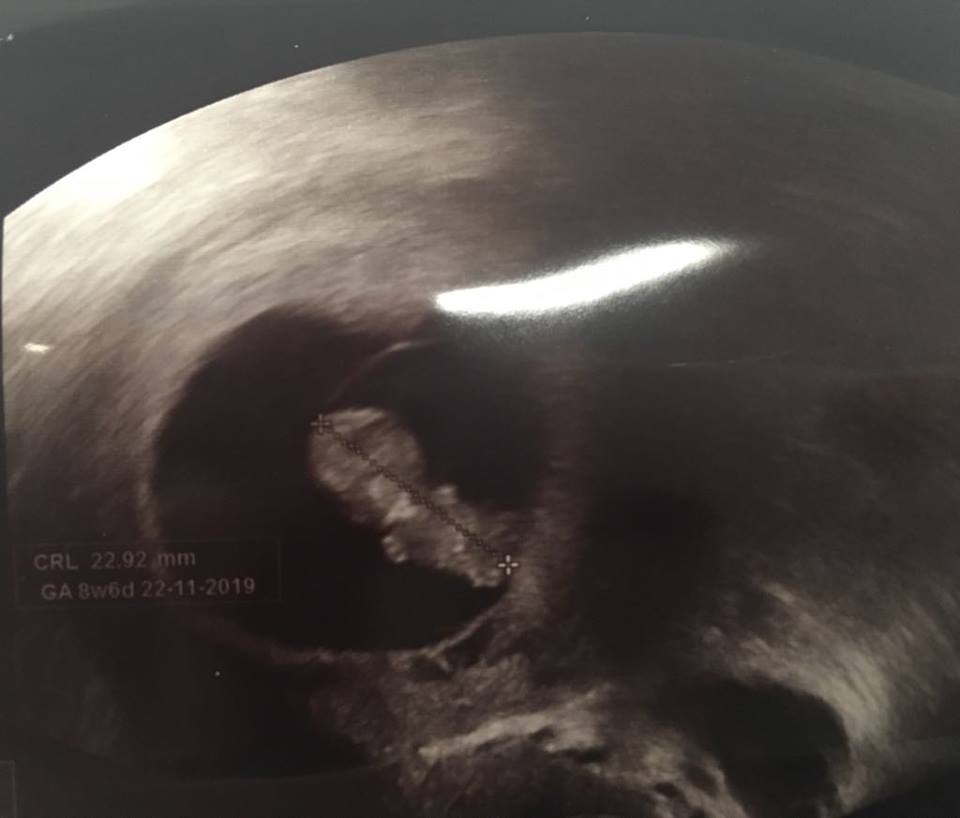

@johan7 taky jsem měla gonal, oni tam snad nic jiného nedoporučují...měla jsem ho malé dávky kvůli PCO, ale celá stimulace v pohodě. Schváleno pojišťovnou máš hned, já tam šla na poslední IUI a rovnou jsme podali žádost a po těch 14ti dnech, co to nevyšlo se rovnou začalo s hormonama..pak tě kontrolují utz a přidávají nebo ubírají...samotný odběr je taky úplně v pohodě, nejhorší je prostě to čekání a toho se nezbavíš ani když se to povede 🙂)) jojo, já byla minulý týden a je to srandovní, už to začíná vypadat jako dítě a přitom to má něco přes dva cm 🙂

@kkacca A kolik Ti to vystimulovalo folikulů? Ježiš, to je boží, prďolka...stejně je to mazec, jak něco tak malinkatýho už je člověk 😀

@johan7 prosim tě, já měla jenom 8folikulů, z toho 4 vejce, jedno nepoužitelný, jedno nedozrálý, takže jenom dvě oplodněné, jenom mám v sobě a jedno je u ledu 🙂 ale já měla fakt hrozně malý dávky, báli se, jak budu reagovat..Jo je to srandovní, před 14ti dny šmouha a ted už mi to začíná bejt podobný :D

@kkacca Jé 😀 to je bobík malej, to vypadá jak ta fotka toho kosmonauta na tom Měsíci 😀

@kkacca 😀 no ne, je krásnej, to sem ale nemusím psát, to vidíme, že jo 😀 ale co hlavně, je ták šikovnej, že už umí i chodit po stěně, to bude veselo 😀 Myslela jsem si, jak bude složité se k němu dostat, ale napsala jsem mu mail a za chvíli na to jsem šla na první konzultaci. Jsem taky ráda, mám z něj fakt strašně dobrej pocit.